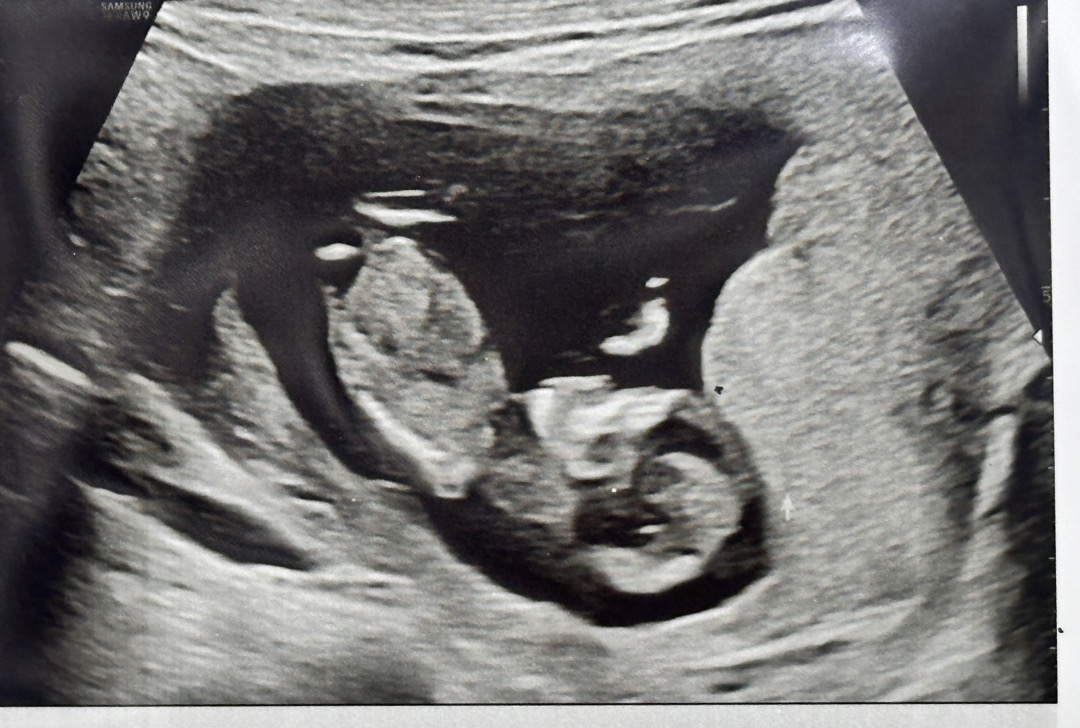

13주차 아기성별

12주차 정밀초음파에서 선생님도 다리사이가 매끈하다고 딸인것같다고하셨고 각도법이나 입덧때 땡기는 음식,고기못먹는거 이런거때문에 딸이라고 거의 확신을 하고있었는데 오늘 니프티검사결과 문자로 아들이 나왔어요 너무 얼떨떨하고 믿기지가않아서 초음파 동영상 다시보는데도 다리사이에 정말 아무것도안보이고 매끈해서 니프티결과 나왔는데 오히려 마음만 더 복잡해져버렸네요ㅜㅜ찾아보니 성별반전인 경우도많고,,,어떤걸 믿어야할지ㅜㅜ결국 16주차까지 시간을 보낼수밖에 없는거겠죠